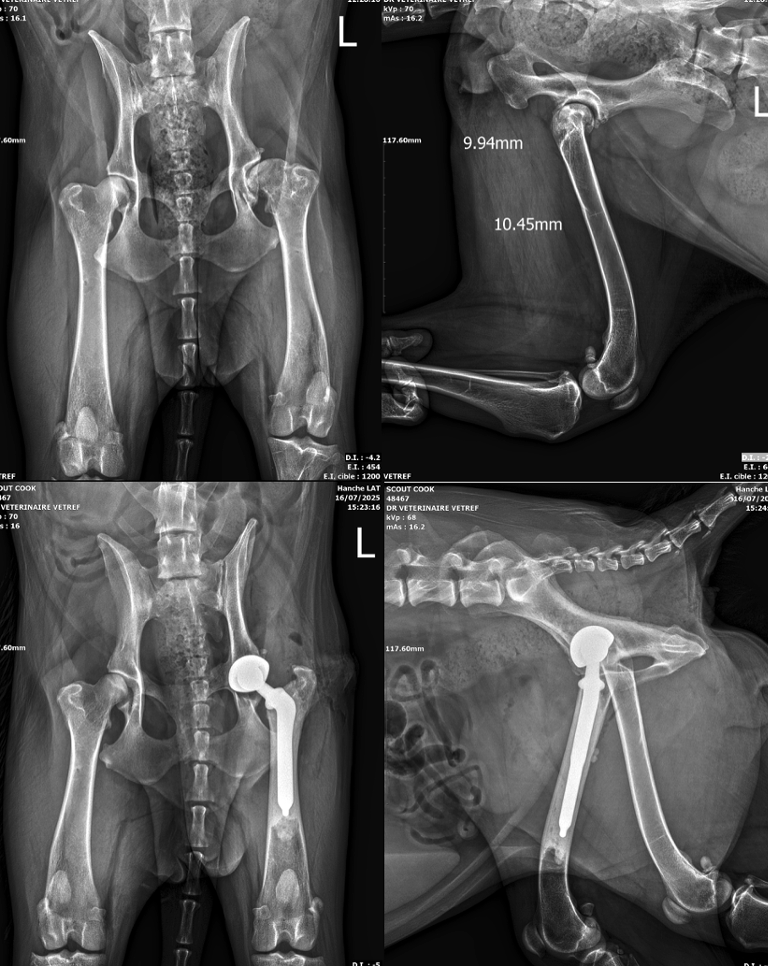

• Prothèse de hanche

Prothèse de hanche